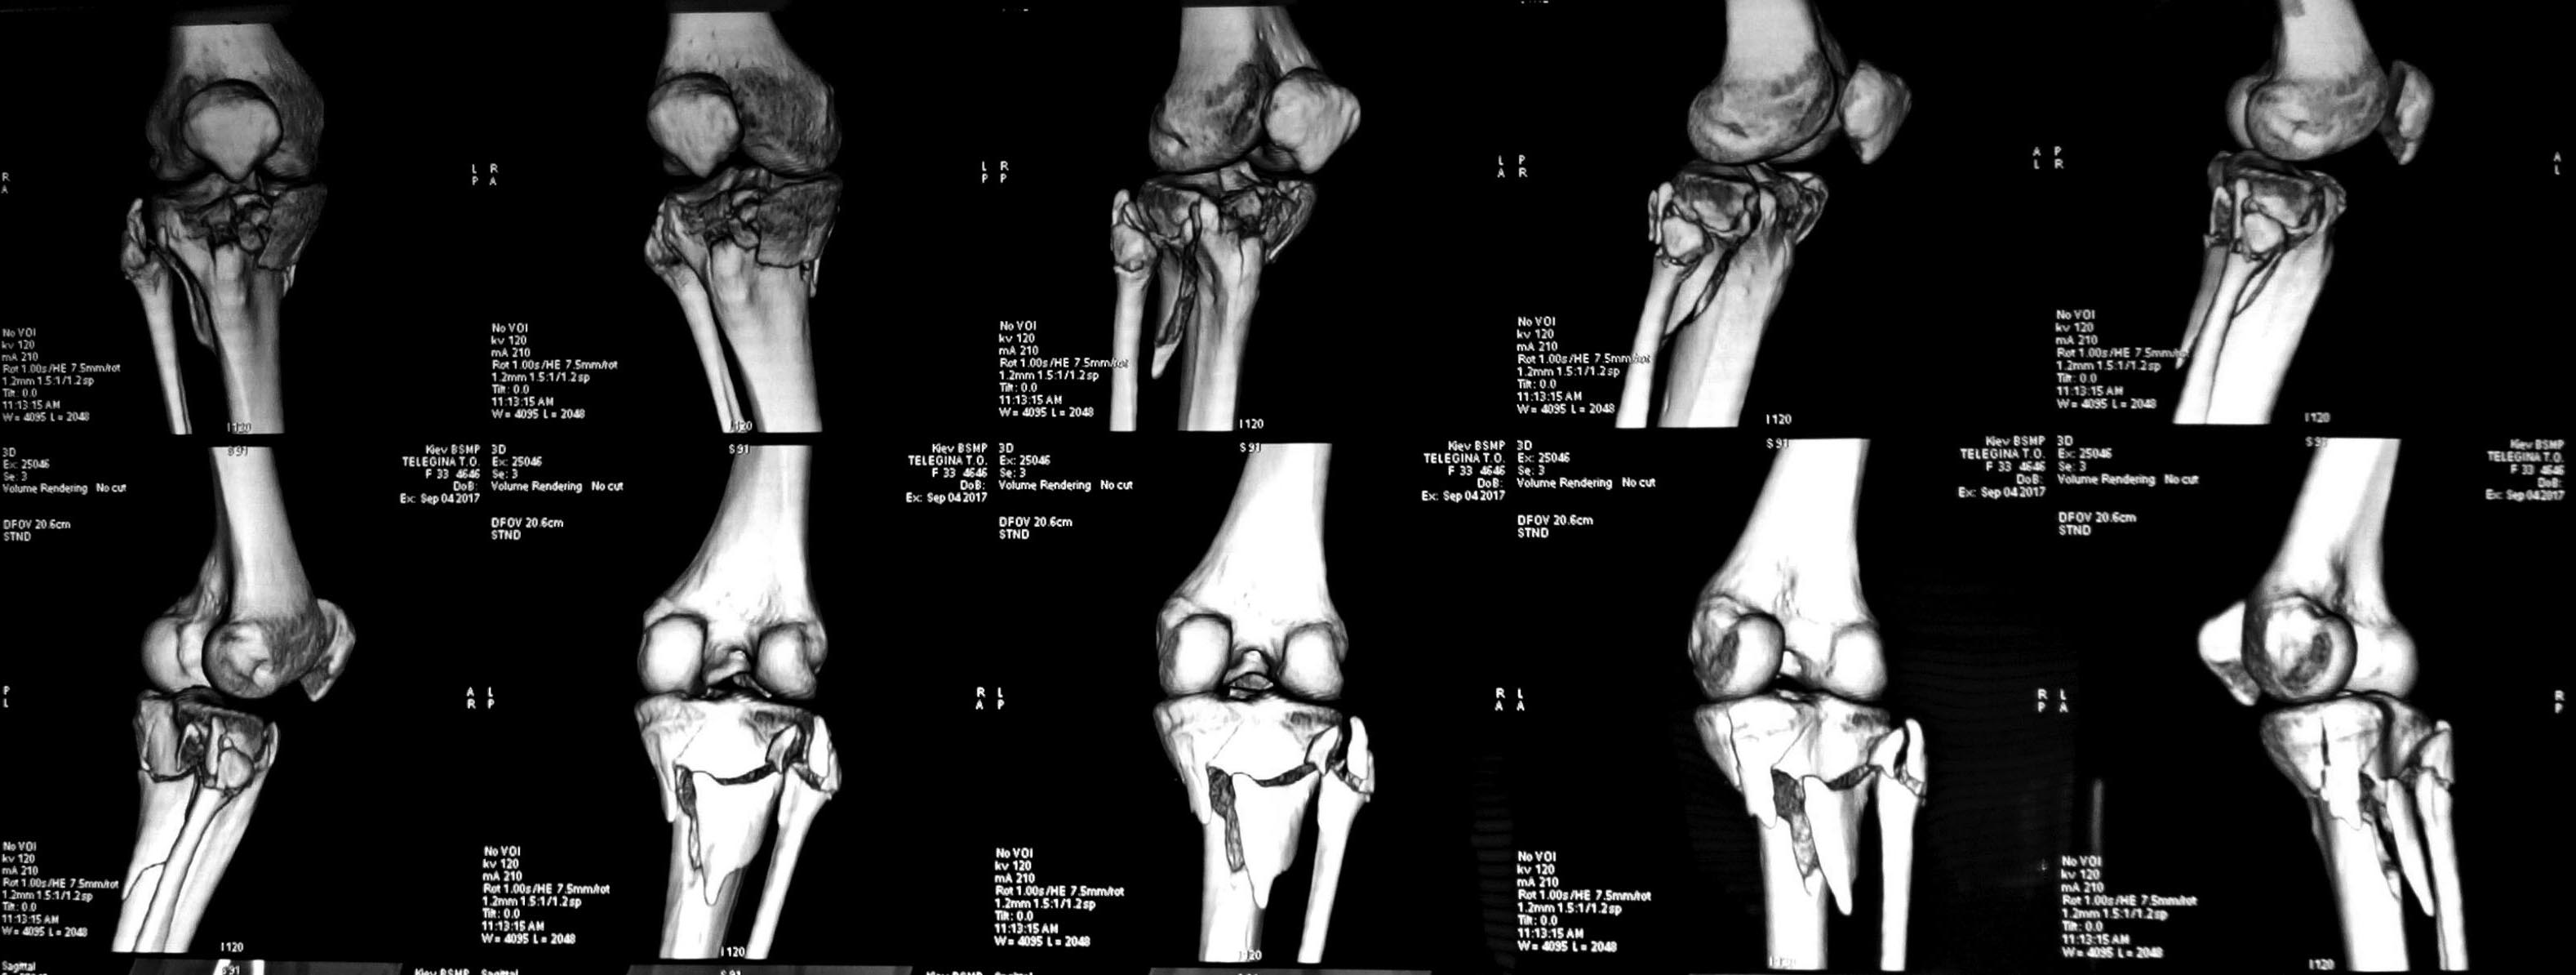

Добрый день, дорогие коллеги, прошу совета. Молодая пациентка с

переломом ПЭМ голени, фрагментацией fibular head и нейропатией peroneal

n.(подобное сочетание у нас не часто). Мягкие ткани компенсированы,

планируется реконструкция из 2-х доступов, однако

разделились мнения касательно целесообразности ревизии нерва,репозиции и

фиксации перелома fibular head. Считаю, что для ранней функции репозиция

и укрепление коллатерального комплекса необходимы. Спасибо.